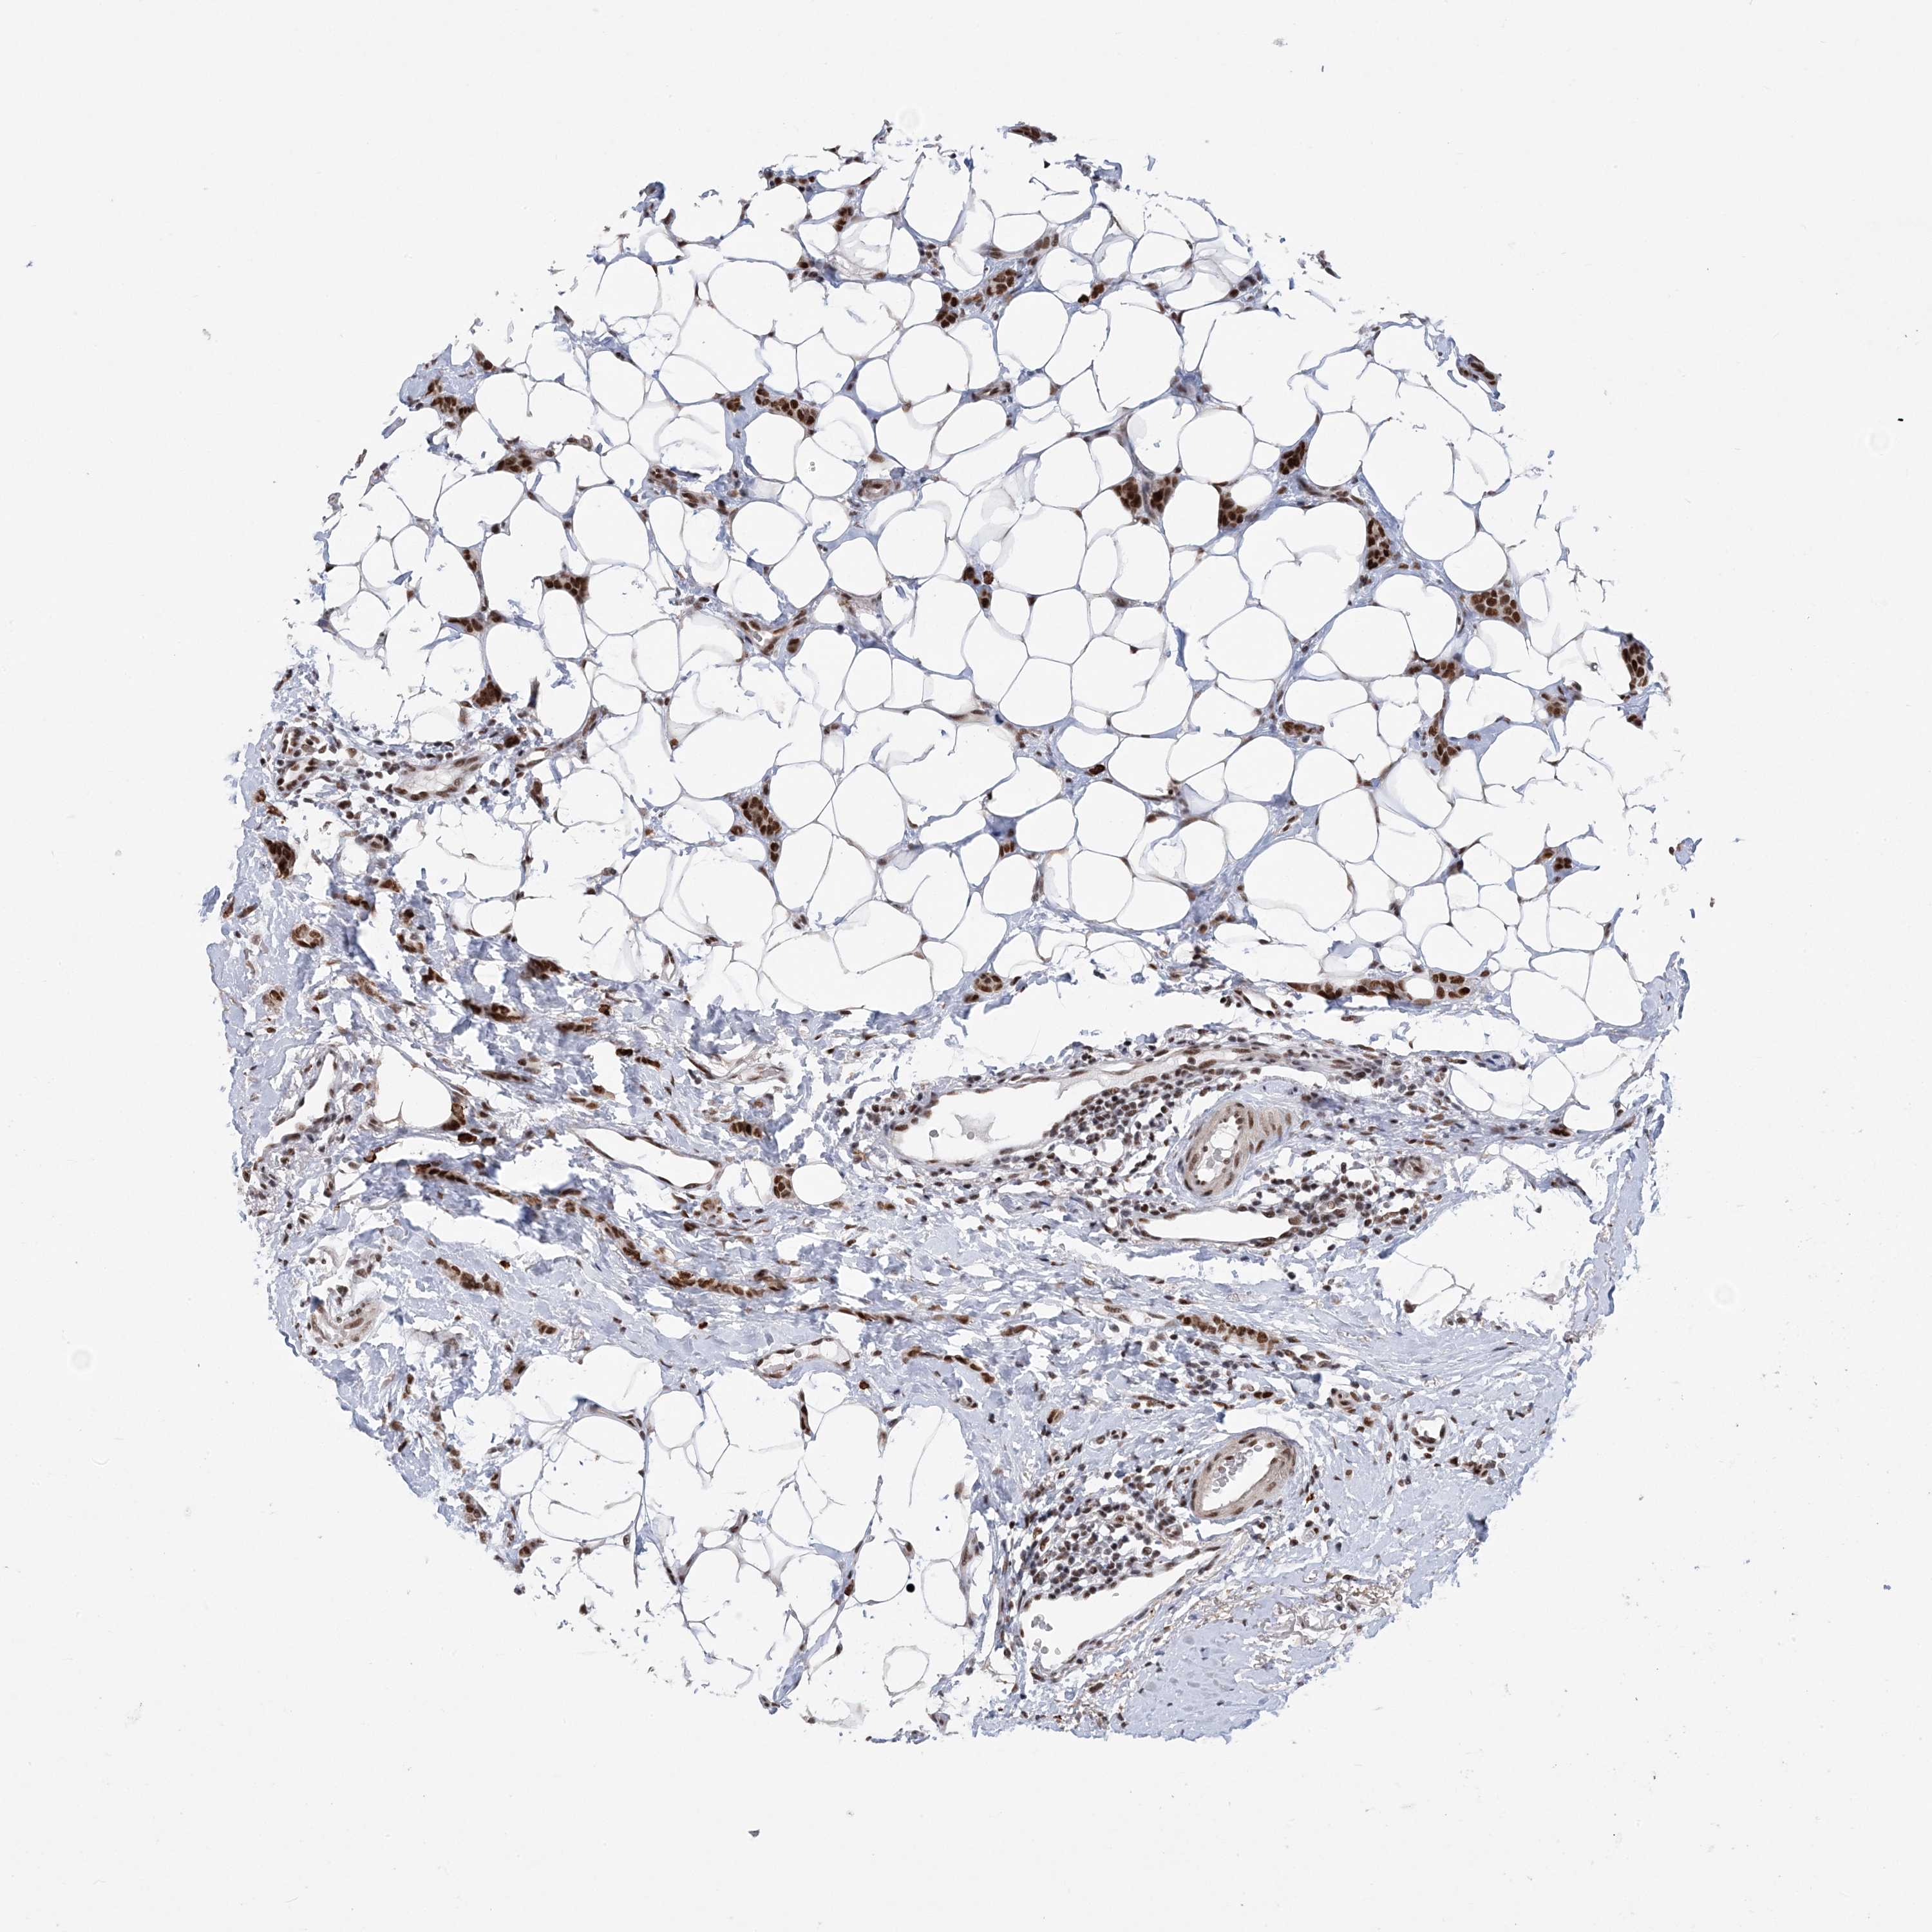

CANCER BREAST CANCER Show tissue menu

BRCA TCGA BRCA VALIDATION PROTEIN EXPRESSION